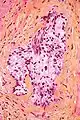

صورة مجهرية توضح الغزو حول العصب. صبغة الهيماتوكسيلين والأيوزين.